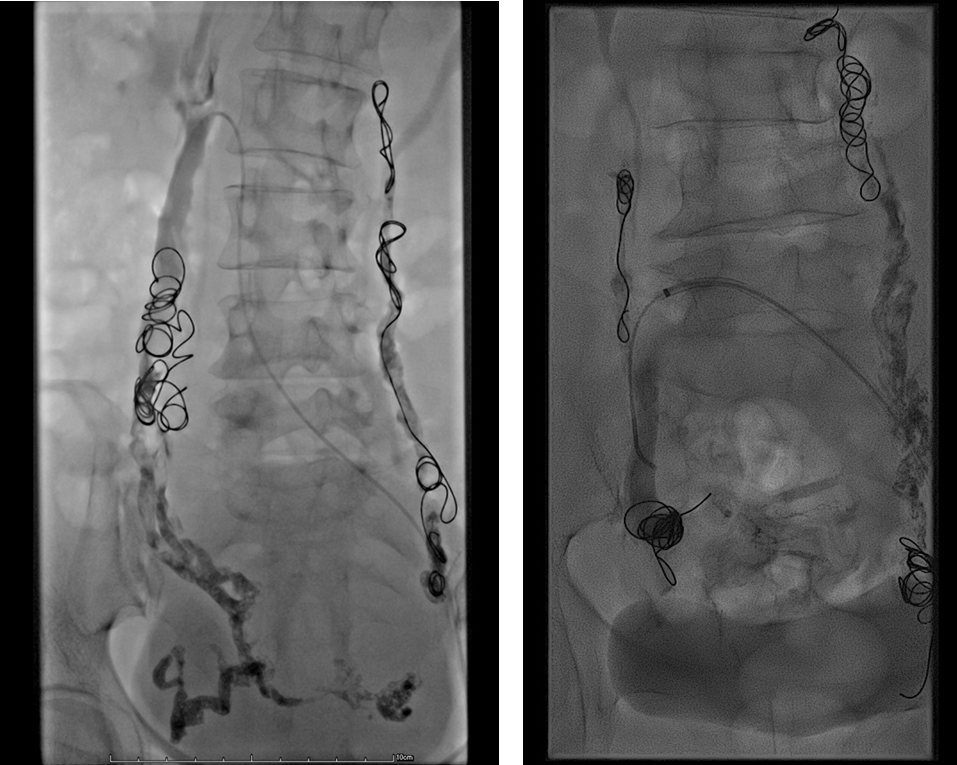

中山经验:“节约型三明治技术”

Sandwich技术优化-节约版

GLUBRAN替代Onxy;

双股静脉入路:可调弯鞘解决反流支;

减少可控圈以及微导管使用;

减少费用;

减少照射;

减少移位;

减少复发;

需解决技术问题:液体栓塞材料溢流。

示例(D-IIV)

示例(LOV+LCV)